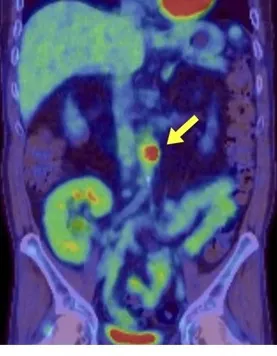

Na investigação de quadro de lesões de pele e calcificação extra-esquelética, observou-se um tumor calcificado no átrio esquerdo, bem como lesões ateroscleróticas calcificadas na aorta, artérias ilíacas e femorais, além de depósitos de cálcio no tecido subcutâneo e lesões na pele (figura abaixo).

Além disso, a investigação revelou uma baixa fração de excreção de fósforo, bem como níveis elevados de FGF23 (51 pg/mL, com o valor de referência <30 pg/mL) e C-terminal FGF23 (151 pg/mL, com o valor de referência <100 pg/mL).